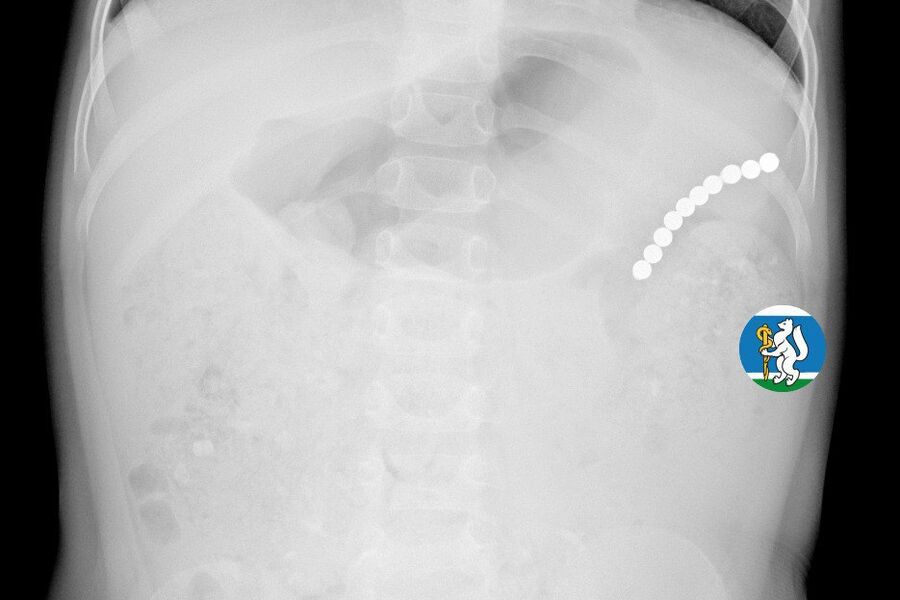

Девочка рассказала родителям о плохом самочувствии, и те показали ее врачам. Медики направили пациентку на рентген грудной клетки. Благодаря обследованию специалисты обнаружили в проекции желудка цепочку магнитов, соединенных между собой. Ребенку сразу же госпитализировали и оказали помощь.

«Для минимизации риска осложнений удаление инородных тел было проведено интраоперационно. В ходе вмешательства дежурная бригада врачей извлекла 10 магнитных шариков, цепочка которых в длину составила 5 сантиметров», — рассказал детский хирург ДГКБ №9 Андрей Чукреев.